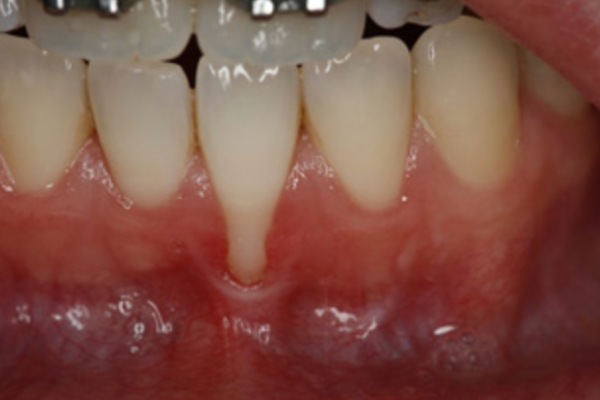

Gum recession exposes the roots of your teeth, leading to sensitivity and an increased risk of decay. We offer gum grafting procedures to restore lost gum tissue and protect your teeth.

If your gums are receding and exposing the roots of your teeth, you may need gum grafting to prevent further damage and sensitivity. Your dentist will assess your condition and recommend the best treatment.